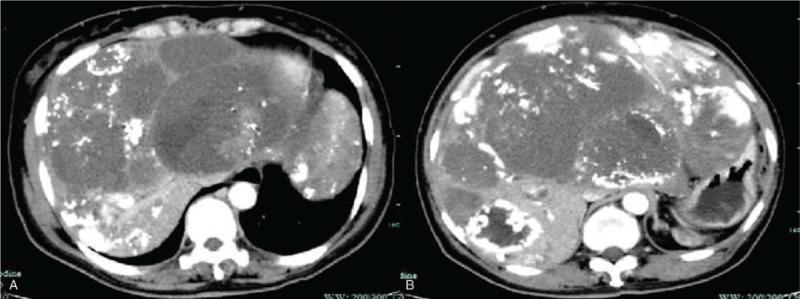

We reported a case of a 51-year-old woman with splenectomy 4 years ago and the postoperative histopathology diagnosis revealed "splenic hemangioma" with spontaneous rupture. Two years after the operation, the patient's rechecked abdominal computed tomography (CT) showed multiple hepatic occupations.

我们报告了一例51岁女性患者,4年前接受了脾切除术,术后组织病理学诊断为“脾血管瘤”且发生了自发性破裂。术后两年,患者复查腹部计算机断层扫描(CT)显示肝脏有多处占位。